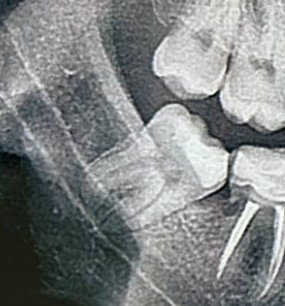

1000070961.jpg 180Кб, 882x704

882x704

Зуб пятерка. Возможно такое вылечить, анонче? Отклолся как то, вообще не болит.

Аноним 11/08/25 Пнд 15:56:42 1635620 36